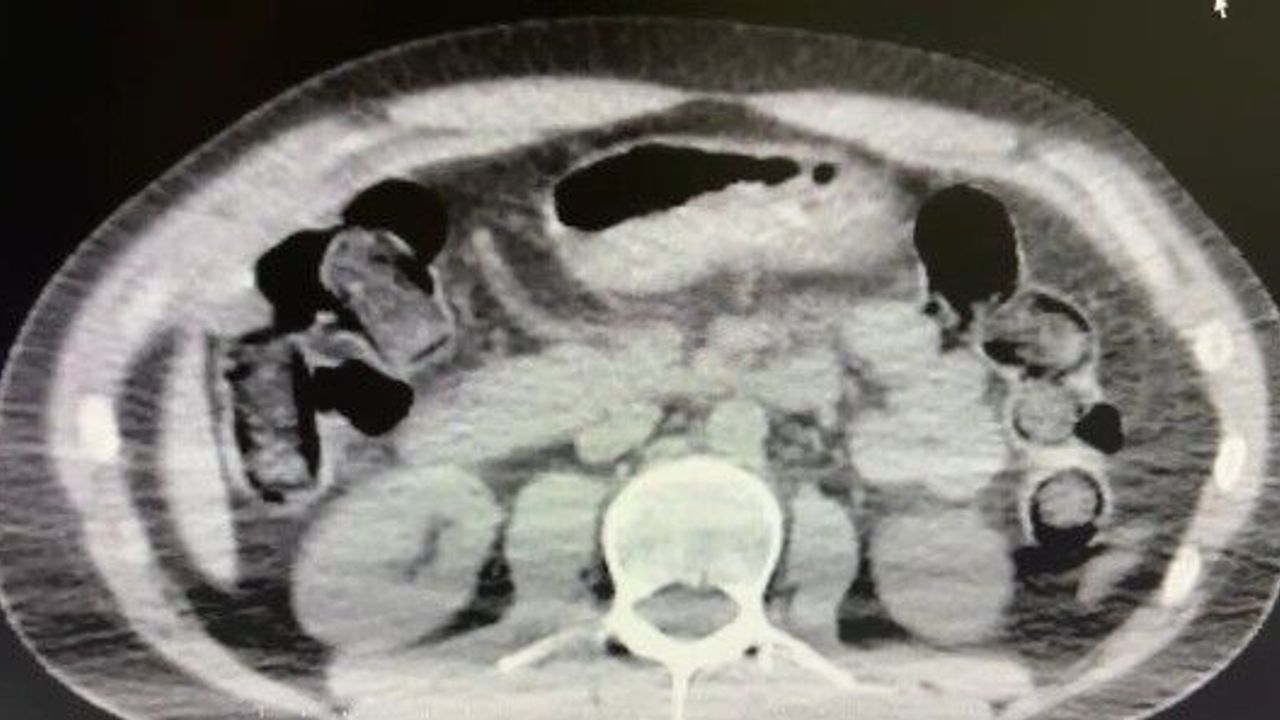

Nevşehir İl Emniyet Müdürlüğü Narkotik Suçlarla Mücadele Şube Müdürlüğü ekipleri, kentte uyuşturucu ve uyarıcı madde ticareti yapmak ve kullanmak suretiyle vatandaşları zehirleyen sokak satıcılarına yönelik çalışma başlattı. Cumhuriyet Başsavcılığı koordinesinde çalışmalarını yoğunlaştıran ekipler, şüpheliler S.B. ve O.R.'nin 'yutma yöntemi' ile kente uyuşturucu madde sevk edeceği bilgisi üzerine operasyon düzenledi. Şüphelilerin ikametlerinde ve araçlarında yapılan aramada 101 kapsül halinde 722 gram uyuşturucu madde, 1 adet hassas terazi, uyuşturucu madde sevkiyatında yutma yönteminde kullanılan muhtelif materyaller, uyuşturucu madde ticaretinden elde edilen 20 bin 210 TL, bin 320 euro ve 10 ABD doları ele geçirildi. Emniyetteki işlemlerinin ardından adliyeye sevk edilen 2 şüpheli, çıkarıldıkları mahkemece tutuklanarak cezaevine gönderildi.